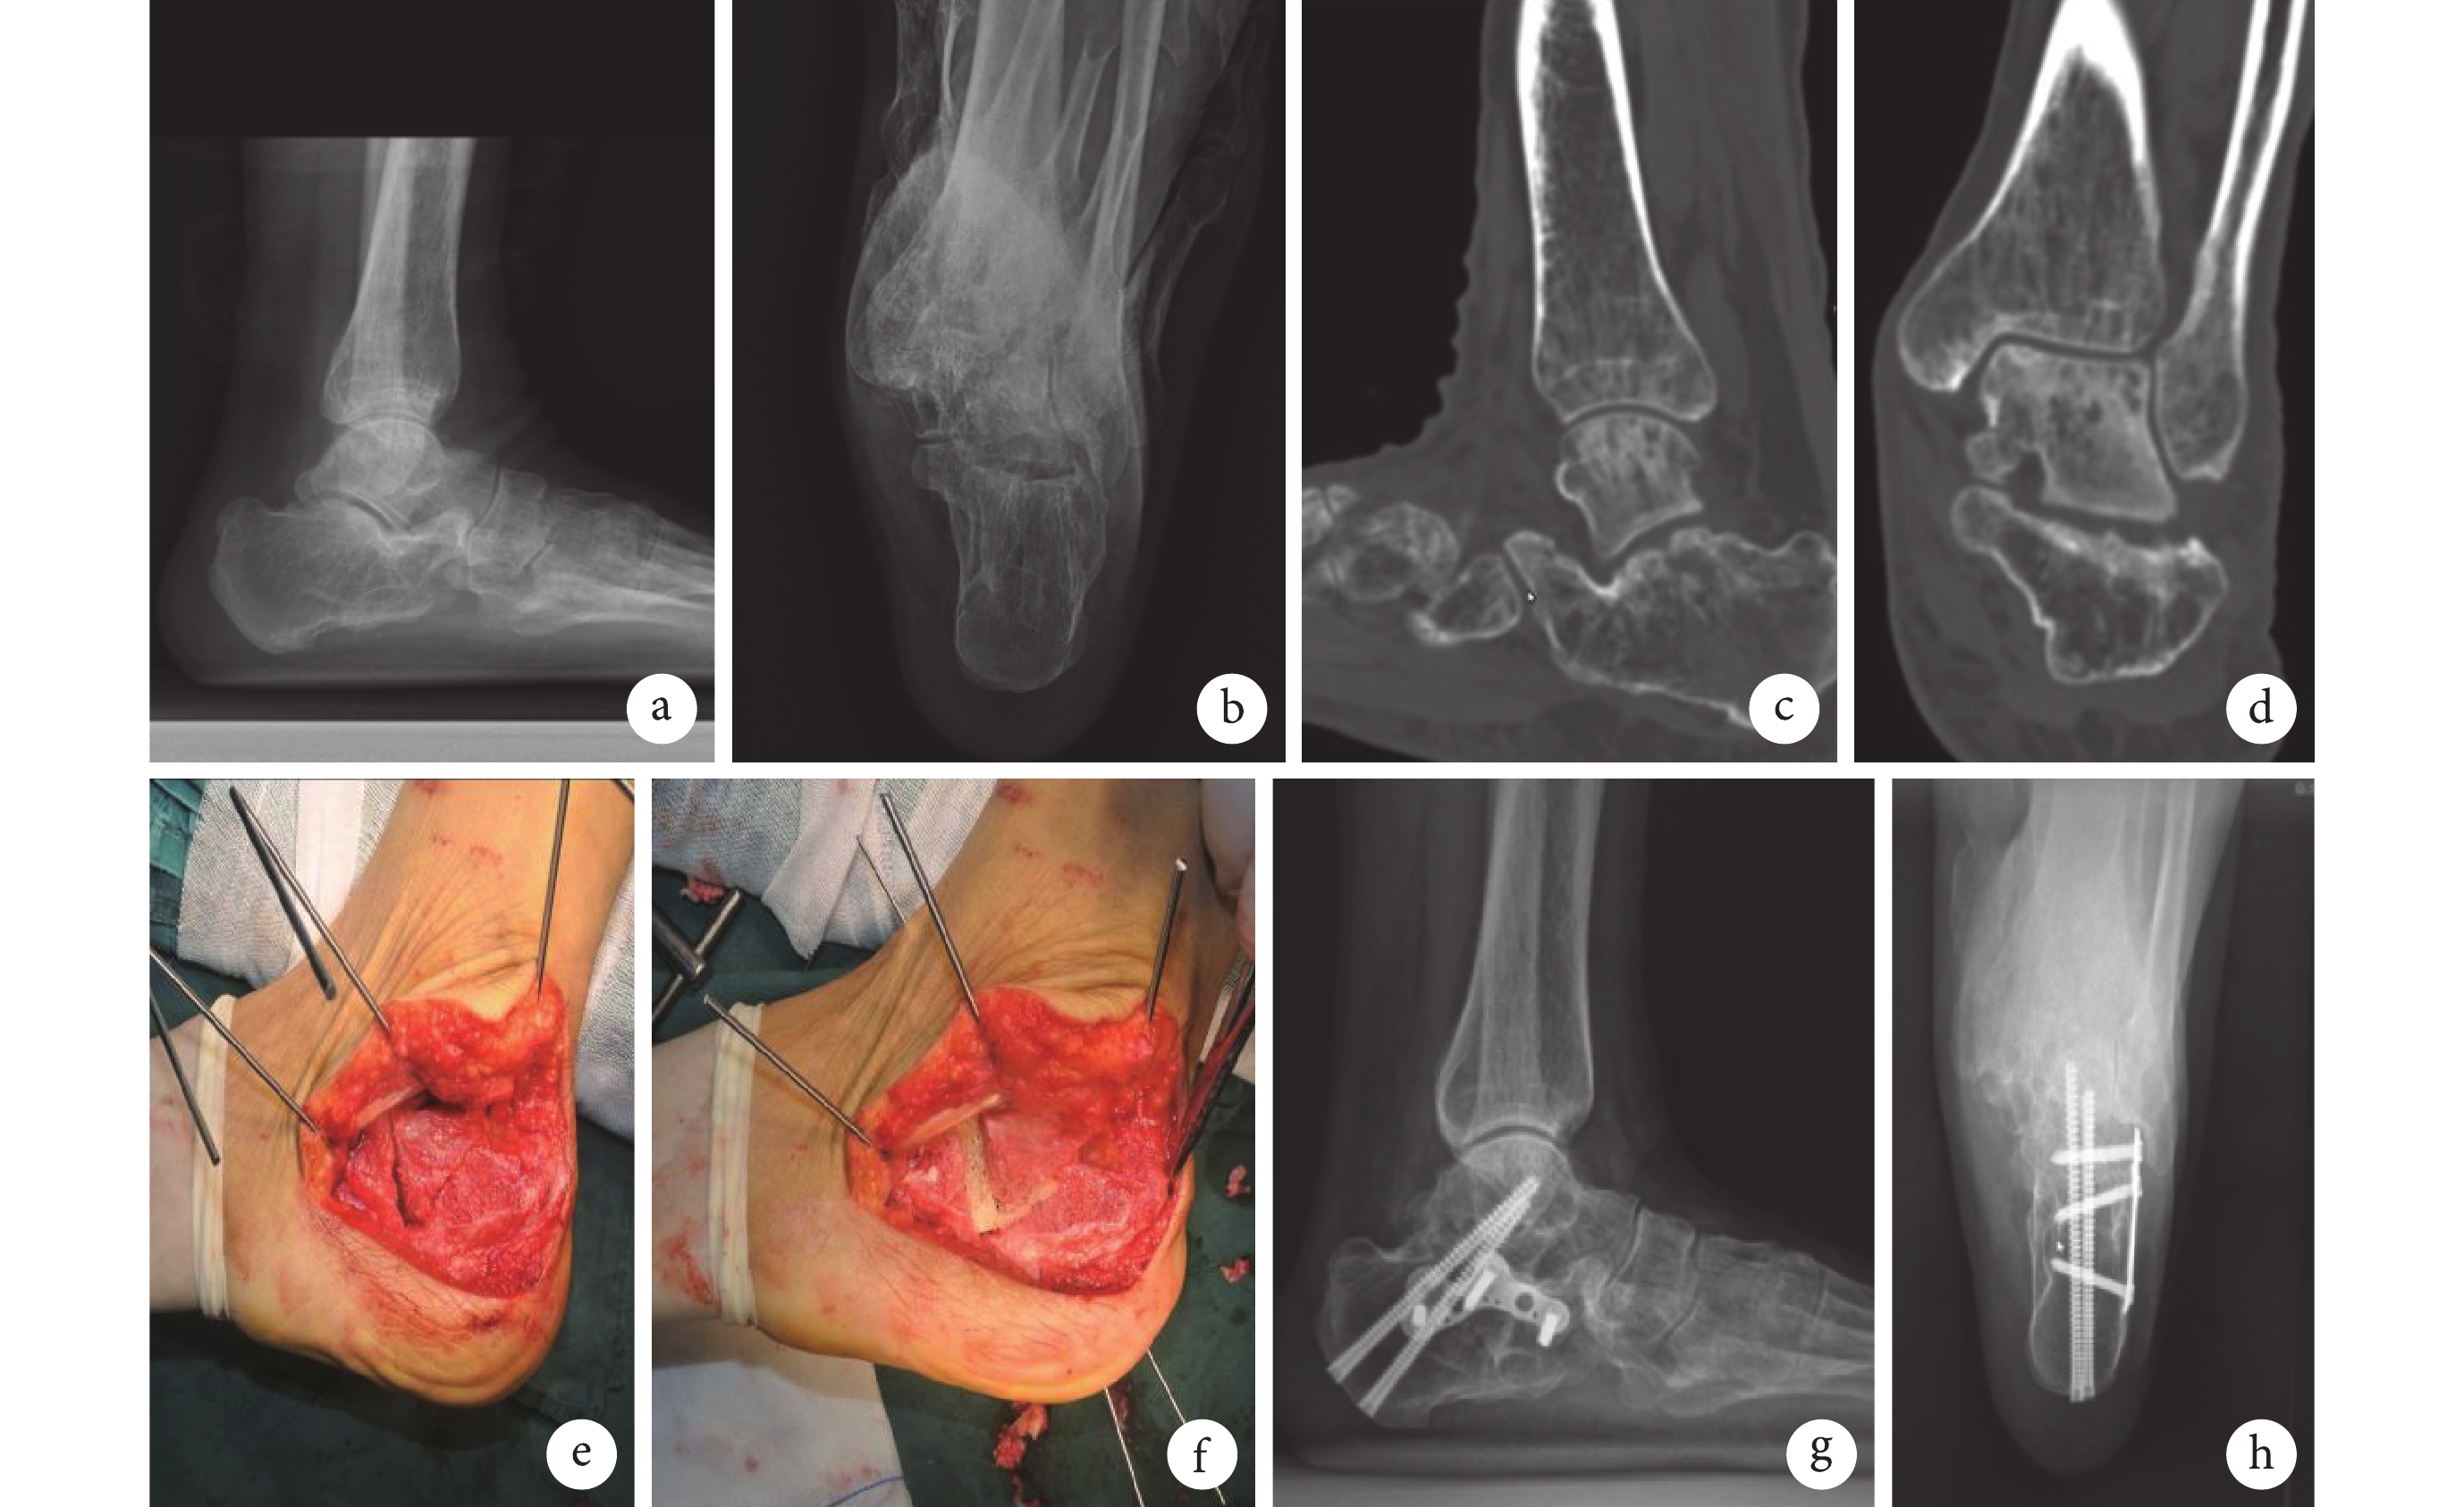

a、b. 術前X線片示跟骨丘部塌陷,距骨水平,后足內翻;c、d. 術前CT示距下關節面嚴重破壞;e. 術中取外側擴大L形切口,切除膨出的跟骨外側壁后行跟骨V形截骨;f. 抬高塌陷的V形骨塊,骨塊間隙使用同種異體骨填充;g、h. 術后12個月X線片示骨性愈合,距跟高度、距骨傾斜角、跟骨寬度及后足力線恢復良好

Figure2. A 47-year-old male patient with Stephens type Ⅱ calcaneal fracture malunion of the left foota, b. Preoperative X-ray films showed collapse of calcaneal thalamus, talus in horizontal position, and hindfoot varus; c, d. Preoperative CT showed severe destruction of subtalar; e. The L-shaped incision was made laterally, and the calcaneal V-shaped osteotomy was performed after excising the extruded lateral wall; f. The V-shaped bone blocks were raised, and the space between the bone blocks was filled with allogeneic bone; g, h. X-ray films at 12 months after operation showed bone healing, and good recovery of talocalcaneal height, talus inclination angle, calcaneal width, and hindfoot alignment